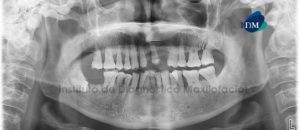

Paciente masculino, 54 años es referido al Instituto de Diagnóstico Maxilofacial para planificación de cirugía guiada con el objetivo de colocar implantes dentales en el